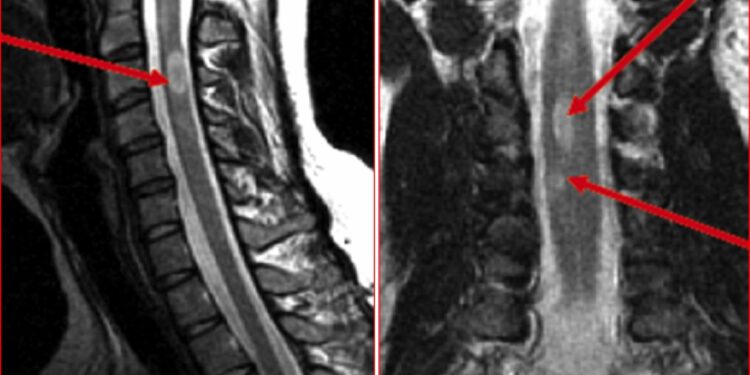

Шейный отдел спинного мозга, который образует шейную часть позвоночника, ближайшую к черепу, является одной из областей, которая особенно страдает при рассеянном склерозе. Большая степень повреждения в этой области связана с более агрессивным течением заболевания и более тяжелым накоплением инвалидности.

В исследовании использовалась передовая методика МРТ, называемая коэффициентом переноса намагниченности (MTR), которая оценивает общую целостность миелина. Потеря миелина была особенно очевидна у пациентов с первично прогрессирующим рассеянным склерозом (PPMS), который характеризуется неуклонным ухудшением симптомов с течением времени.

Результаты показали, что значения MTR, как правило, были ниже у пациентов с PPMS по сравнению со всеми другими тремя группами в ряде областей шейного отдела спинного мозга. Это отражает большую потерю миелина при прогрессирующем рассеянном склерозе.

Важно отметить, что значения MTR обратно коррелировали с общими показателями инвалидности, оцененными по расширенной шкале статуса инвалидности (EDSS), как у пациентов с PPMS, так и с RRMS. В EDSS более высокий балл указывает на худшую инвалидность. Итак, в этом исследовании, чем больше потеря миелина, тем больше инвалидности накопил пациент.